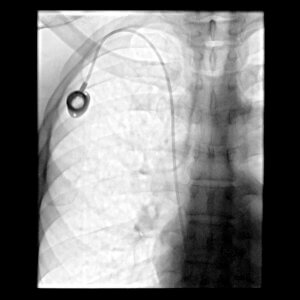

Venous access is an important, if not critical, aspect of the care plan for many patients. Whether it is a patient with cancer requiring chemotherapy, a patient with kidney failure requiring hemodialysis, or a patient with intestinal issues requiring nutritional support, it is their need for venous access which ties all of these patients together. A venous access device (otherwise known as a “catheter” or “line” is essentially a tube that goes inside a vein and can be used to either draw blood samples or administer medication directly to a patient.